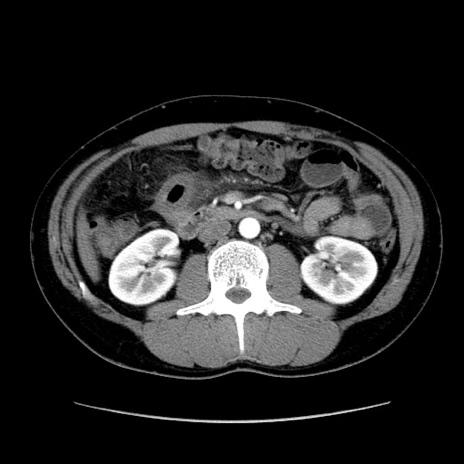

症例36(横断像)

【症例】20歳代 男性

【主訴】心窩部痛

【現病歴】今朝より上腹部痛あり。一旦軽快していたが再度出現したため救急要請。昨日夕に白身の魚を含む刺身を食べた。

【身体所見】BP 136/89mmHg、HR 74/min、BT 37.0℃、腹部:膨満、軟、心窩部に圧痛あり。反跳痛なし、筋性防御なし、腸雑音やや亢進あり。

【データ】WBC 17700、CRP 0.48